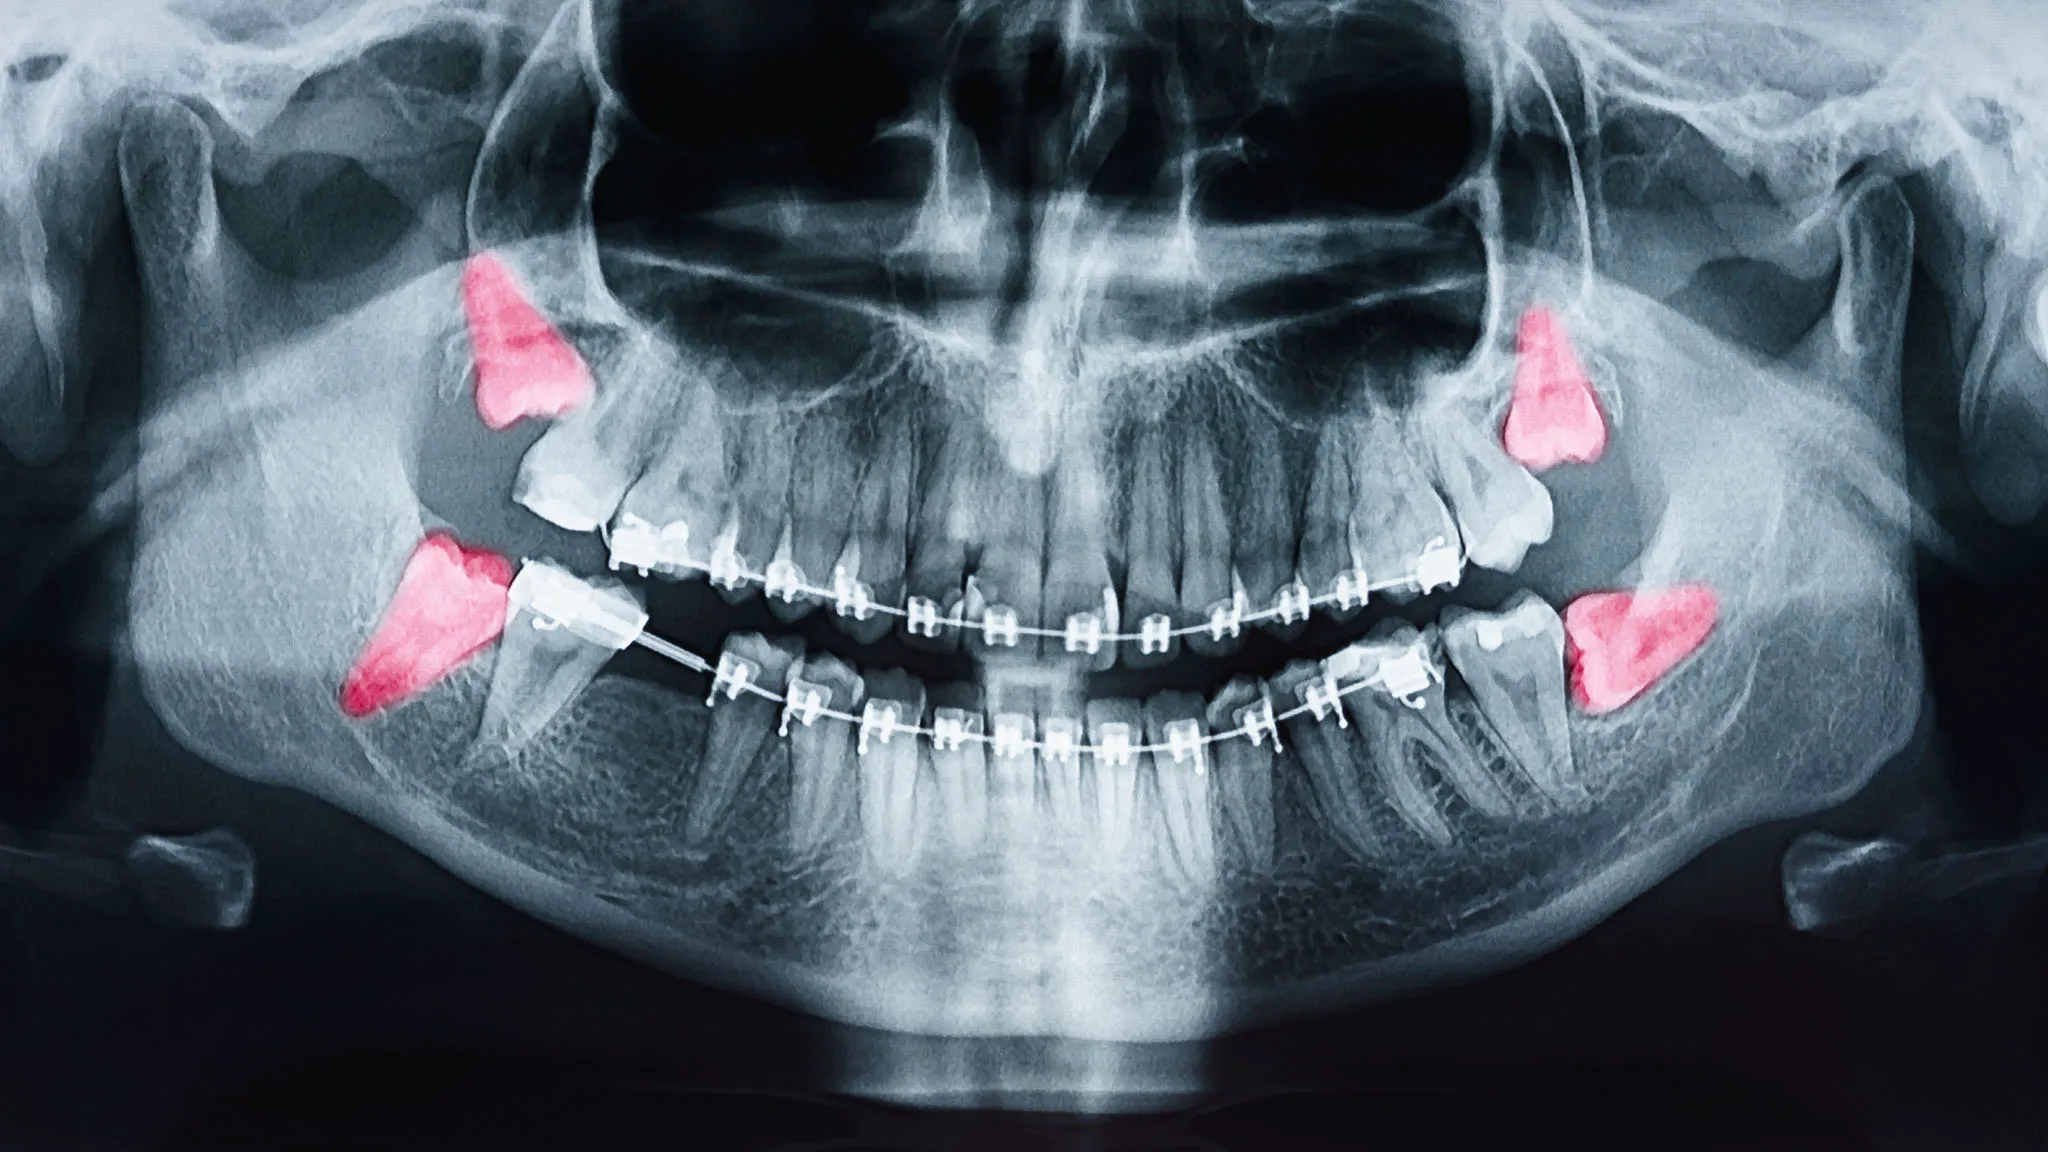

Dr. Sekhon removes wisdom teeth only when they’re causing pain, damage to other teeth, or serious health issues. We like to check on them early during your routine dental check-ups using digital X-rays. This early look helps us spot trouble before it turns into a painful emergency. Taking them out at the right time is the best way to protect your healthy smile.

We take digital x-rays to plan the exact extraction path. We’ll talk about your sedation options and recovery tips.